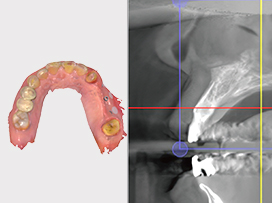

• Systematic Digital Implantology

At Seoul The Nature Dental Clinic, we utilize 3D digital equipment to evaluate each patient's oral condition in detail — including tooth root length, morphology, alveolar bone thickness, and bone density. We develop a fully customized implant placement plan tailored to each patient.